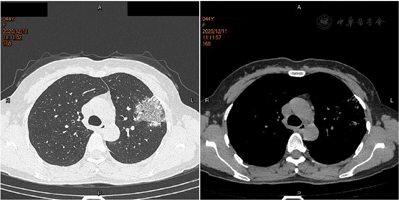

患者,女性,44岁,主因"反复发热6 d"于2020年12月11日入院。患者于6 d前受凉后出现发热,体温最高39.2℃,热型无规律,无畏寒,无寒战,无汗,无咳嗽,无咽痛,无鼻塞、流涕,无味觉、嗅觉减退,无结膜炎,无肌肉酸痛,无乏力,无腹泻,无皮疹。自服退热药(具体药物不详)后体温退至正常,转日体温再次升高,2020年12月7日就诊于我院发热门诊,查血常规+CRP:WBC 6.6×109/L,Neu% 78.2%,Lym% 14.3%,CRP 17.7 mg/L,新冠病毒核酸检测、新冠病毒抗体(IgG+IgM)阴性,胸部CT平扫考虑左肺上叶感染(图1),予头孢克肟口服治疗,仍反复发热。2020年12月11日再次就诊于我院发热门诊,查血常规+CRP:WBC 4.19×109/L,Neu% 73.1%,Lym% 19.3%,CRP 87.7 mg/L,胸部CT平扫:左肺上叶片状磨玻璃状阴影,较前明显增大,考虑炎性病变(图2),以"肺部感染"收入院。刻下症:发热,热型无规律,纳差,眠可,二便调。既往体健,否认慢性病史。末次月经2020年12月3日。